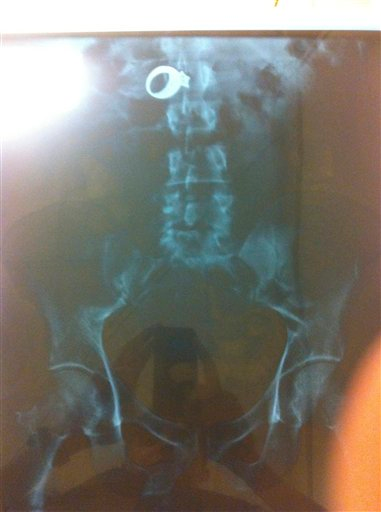

Gonzalez-Cruz was taken to McNeal Hospital, where an x-ray showed the ring in his stomach, according to police.